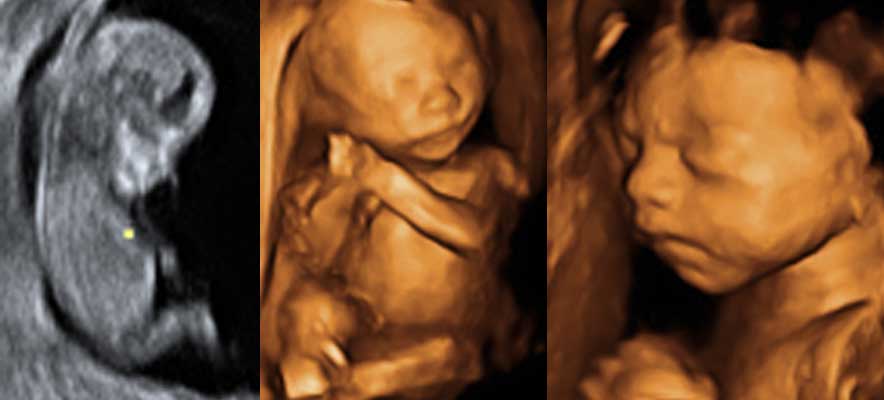

Quirónsalud Madrid cuenta con una unidad específica de diagnóstico de la patología intrauterina con profesionales expertos en el diagnóstico fetal y el apoyo de tecnología de última generación, como la ecografía de alta resolución y la resonancia magnética fetal

. Los profesionales que integran esta unidad (expertos en imagen, obstetras y neonatólogos) mantienen reuniones periódicas para la orientación diagnóstica, actitud terapeútica y consejo de las personas afectadas.

El Servicio de Pediatría cuenta con una consulta específica pediátrica fetal, con gran experiencia en el diagnóstico y consejo de enfermedades de diagnóstico intrauterino, malformativas, con una especial dedicación a alteraciones dismorfológicas y del sistema de nervios central (dilataciones ventriculares, malformaciones etc). Se ofrece consejo en relación al pronóstico y posibilidades terapéuticas.